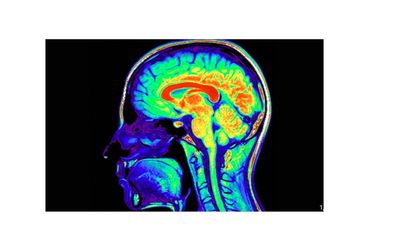

A normal brain has balanced activity and healthy structure, while a brain on drugs shows abnormal reward-center surges and, over time, reduced activity and structural damage.